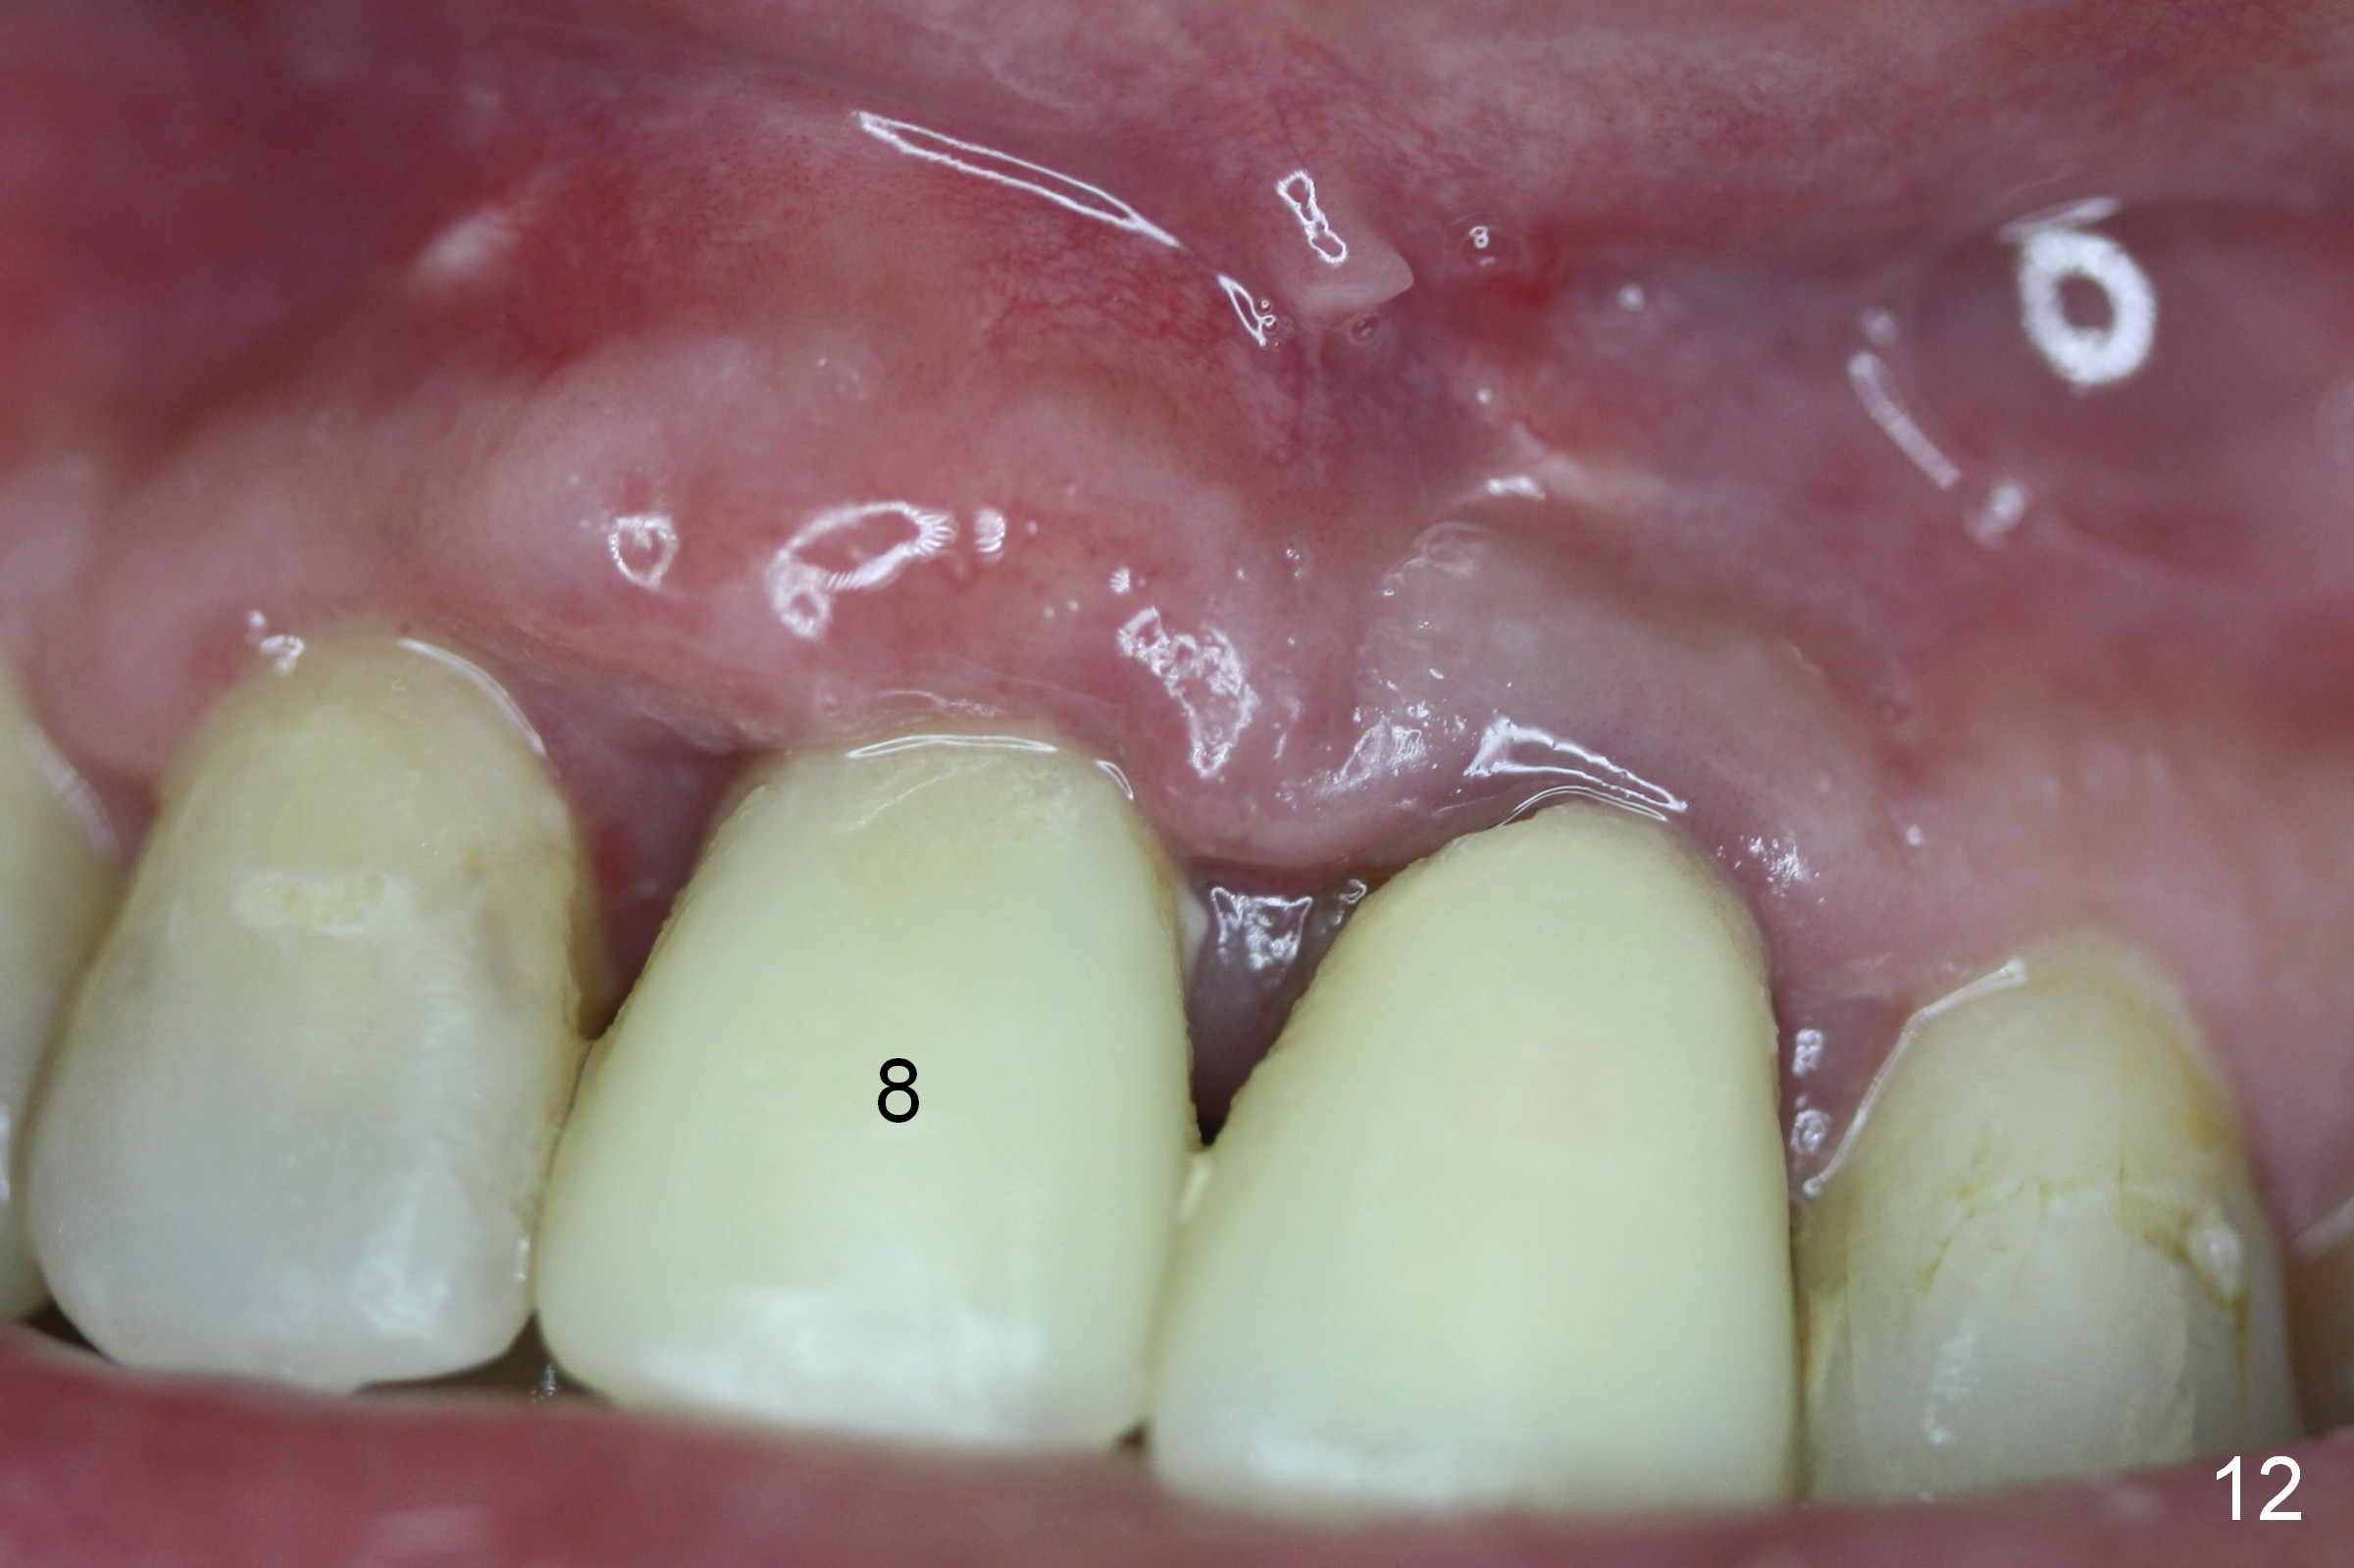

To correct the gingival margin associated with #8 implant, bone graft is needed.  Particulate graft may not stay in place. Chin graft is harvested.  Since the roots of the lower anterior teeth are long (Fig.8), the width of the chin graft is limited for direct screw fixation (Fig.9,10).  Titanium mesh is used for fixation of the graft.  Connective tissue graft from the palate is to increase bulk at the site of #8 (Fig.11 *).  There is no symptom or sign of infection 1 month postop (Fig.12,13).  Although there is alteration of sensation of the lower incisors, there is no apical radiolucency of them 4 months postop (Fig14).  There is no abnormality associated with the bone graft and Titanium mesh (Fig.15).

Nine months postop, the gingival margin is symmetrical over the provisional crowns at #8 and 9 (Fig.16).  There is no bulging or concavity associated with the implant at #8 (Fig.17).  Screw (Fig.16 <) removal is scheduled prior to final restoration.  The gingiva is healthy 1 year 7 months post cementation (Fig.18).